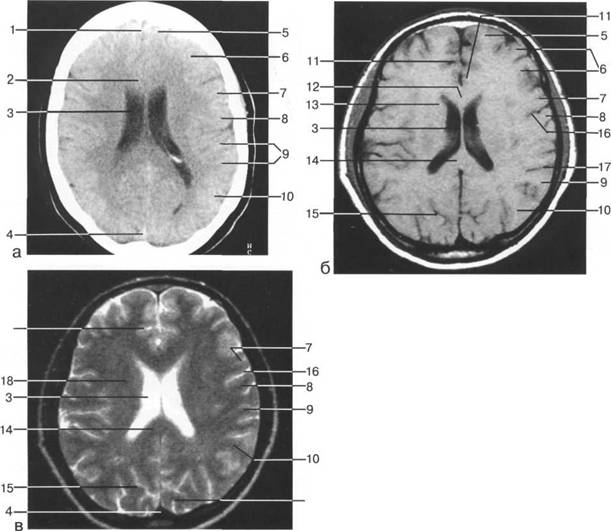

цистерна четверохолмия; 14 -прямой синус; 15 -лобный рог; 16 - головка хвостатого ядра; 17 -перед

III ди зрительного бугра идет ретроталамическая цистерна, ориентированная во фронтальной

проведенной от наиболее дистальной точки затылочного рога к костям свода череп 13513u2010n 72;. Считает

теменно-затылочная борозда; 11 - семиовальные

(planum),